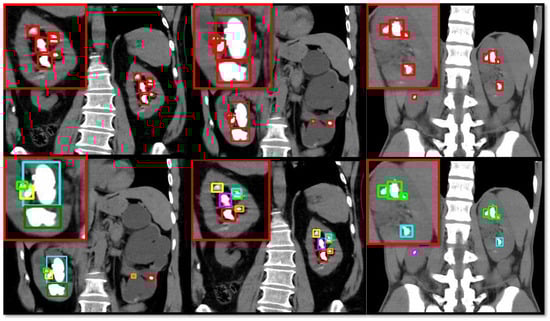

4.5. Different Coloring Approaches

Figure 4 illustrates the application of a different color approach for our proposed model to distinguish closely located kidney stones and avoid confusion resulting from overlap. The first row of images displays the kidney stone detection results using a standard method, with red boxes highlighting the detected stones. These red-highlighted boxes are sometimes very close to each other, potentially leading to misunderstandings of the detection results and creating an impression of an overlap. To address this issue, the second row employs a color-coding scheme to improve clarity. Each detected stone was highlighted with a uniquely colored box (green, blue, yellow, purple, and red), allowing clear differentiation between closely spaced stones. This approach effectively resolves any potential overlapping issues observed in the first row, making it easier to identify and count the stones. This enhanced visualization method provides a clearer and more precise a presentation of the kidney stone detection results, facilitating a better analysis and understanding of the detection performance of different models.

Figure 4.

Different coloring approaches for boundary boxes of detected objects.

One of the primary post-processing steps we implemented is a novel color-coded bounding box scheme. This method assigns unique colors to closely located stones, particularly when they overlap in the CT images. The purpose of this approach is to resolve potential ambiguities caused by overlapping bounding boxes, which can occur when multiple stones are located near one another. By visually differentiating each detected stone, the model output becomes clearer, facilitating easier interpretation and reducing misclassification in cases where stones are tightly clustered. To further address the issue of overlapping stones, we employed a bounding box merging strategy during post-processing. This approach involves analyzing predicted bounding boxes with a high intersection over union (IoU) score. When the IoU between two bounding boxes exceeded a set threshold (in our case, 0.45), we merged these bounding boxes to form a single, consolidated prediction. This technique helps avoid redundant or erroneous detections that may arise from noise or small, irregular stones being detected multiple times in slightly different locations. By refining the bounding boxes in this manner, the overall detection accuracy is improved, particularly in cases where stones overlap or are located in complex anatomical regions.